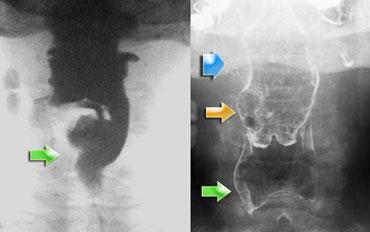

Nuốt bất đối xứng do xoay đầu. Đầu xoay sang trái và thuốc cản quang chỉ thấy ở kênh thức ăn bên phải.

Bất đối xứng

Nuốt bất đối xứng trên tư thế thẳng (AP) thường là kết quả của sự nghiêng không đều của nắp thanh quản.

Đôi khi nguyên nhân là do xoay đầu, nhưng trong nhiều trường hợp không tìm được giải thích thực sự.

Ngay cả khi đầu không xoay, nắp thanh quản vẫn có thể nghiêng bất đối xứng khi chạm vào thành hầu sau.

Điều này dễ xảy ra hơn khi chỉ cho một lượng bolus nhỏ, vì hầu họng sẽ không giãn nở hoàn toàn.

Một bolus lớn hơn sẽ tạo ra động tác nuốt đối xứng.

Trong trường hợp bên trái, việc xoay đầu sẽ đóng phía mà đầu xoay về (Hình).

Nếu bệnh nhân bị liệt hầu một bên, việc xoay đầu về phía bên bị tổn thương sẽ giúp bệnh nhân phòng ngừa hít sặc.

Bằng cách xoay đầu về phía bên bị tổn thương, phía này sẽ bị đóng lại, ngăn ngừa ứ đọng ở phía này và khả năng hít sặc thứ phát.

Tuy nhiên, trước khi kết luận đây là dấu hiệu bình thường, cần loại trừ khối u hầu họng hoặc liệt một bên.

Hình ảnh đối quang kép có thể hữu ích trong những trường hợp này.

Trong liệt một bên, phía bị liệt sẽ phồng ra trong nghiệm pháp Valsalva cải tiến.

Khi có khối u trong hầu họng, thường có thể thấy trên hình ảnh đối quang kép.

Đôi khi cần nội soi để giải quyết vấn đề nuốt bất đối xứng.

Bất đối xứng (2)

Trường hợp bên trái là một ca bệnh đặc biệt, nhưng minh họa rõ nét sự khó khăn đôi khi gặp phải trong việc xác định nguyên nhân gây bất đối xứng.

Ở hình ngoài cùng bên trái, bất đối xứng được thấy trên nghiên cứu huỳnh quang (mũi tên xanh lá).

Có vẻ như có gì đó trong xoang lê bên phải.

Trên hình ảnh đối quang kép bên phải, xoang lê bình thường (mũi tên xanh lá), nhưng ở mức thung lũng nắp thanh quản bên phải thấy một tổn thương dạng thùy (mũi tên vàng).

Ở mức cao hơn, thấy một vết lõm nhẵn của hầu miệng (mũi tên xanh dương).

Khối u dạng thùy ở mức thung lũng nắp thanh quản được xác định là phần còn lại của amidan lưỡi, đây là phát hiện thường gặp và đôi khi khó phân biệt với ung thư đáy lưỡi.